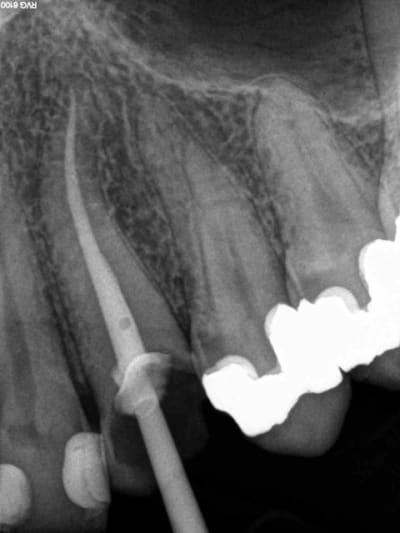

mon 3D kodak

un peu cherot effectivement mais revolutionne mon exercice en endo et évite les galères

un vision claire du nombre et de la disposition des canaux ainsi que de leur longueur réelle , je n'aurais jamais osé rêver çà ...